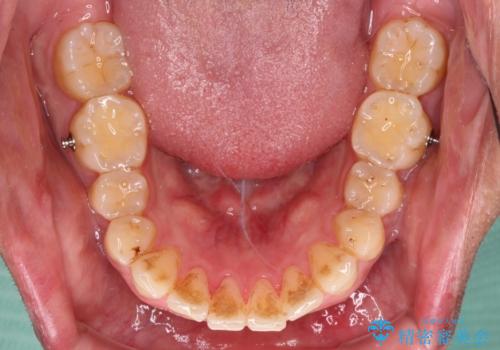

配属異動や長時間勤務などによりインビザラインが十分に装着できない期間があり、インビザライン有効期限5年間ギリギリとなってしまいました。